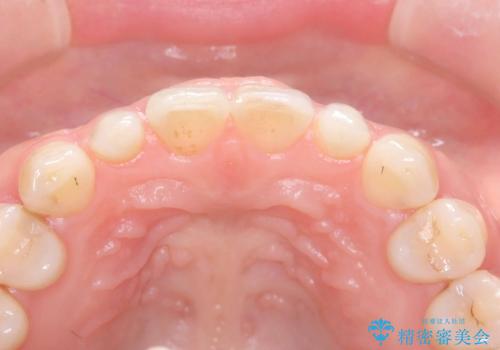

- 歯並びを矯正で整えたあと、上顎左右2番の歯(前歯の横の歯)の「矮小歯(歯が小さい状態)をオールセラミッククラウンで審美修復した症例です。

矮小歯はもともと歯が小さいため、削る量を最小限に抑えた負担の少ない治療が可能です。